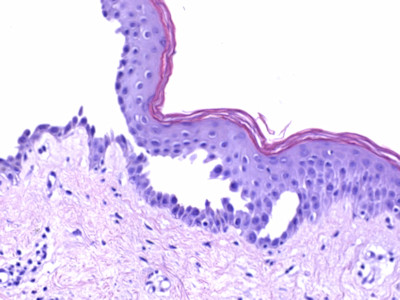

Aanvullend onderzoek:

Histologie (biopt met daarin een randje van de blaar voor

HE, de IF uit de normale peri-lesionale huid); vroeg stadium: spongiotische

dermatitis met oedeem vooral laag in de epidermis. Later suprabasale acantholyse

met vorming van intra-epidermale splijting en blaren, ook in de follikels. Basale

cellen splijten van elkaar, niet van de basale laag waardoor de basale keratinocyten

een 'thombstone' (grafstenen) aspect hebben. De blaarholte bevat acantholytische

keratinocyten, fibrine, en eosinofiele granulocyten. Geen / weinig dyskeratotische

cellen. Dermis: superficieel gemengdcellig perivasculair en interstitieel infiltraat

met veel eosinofiele granulocyten.